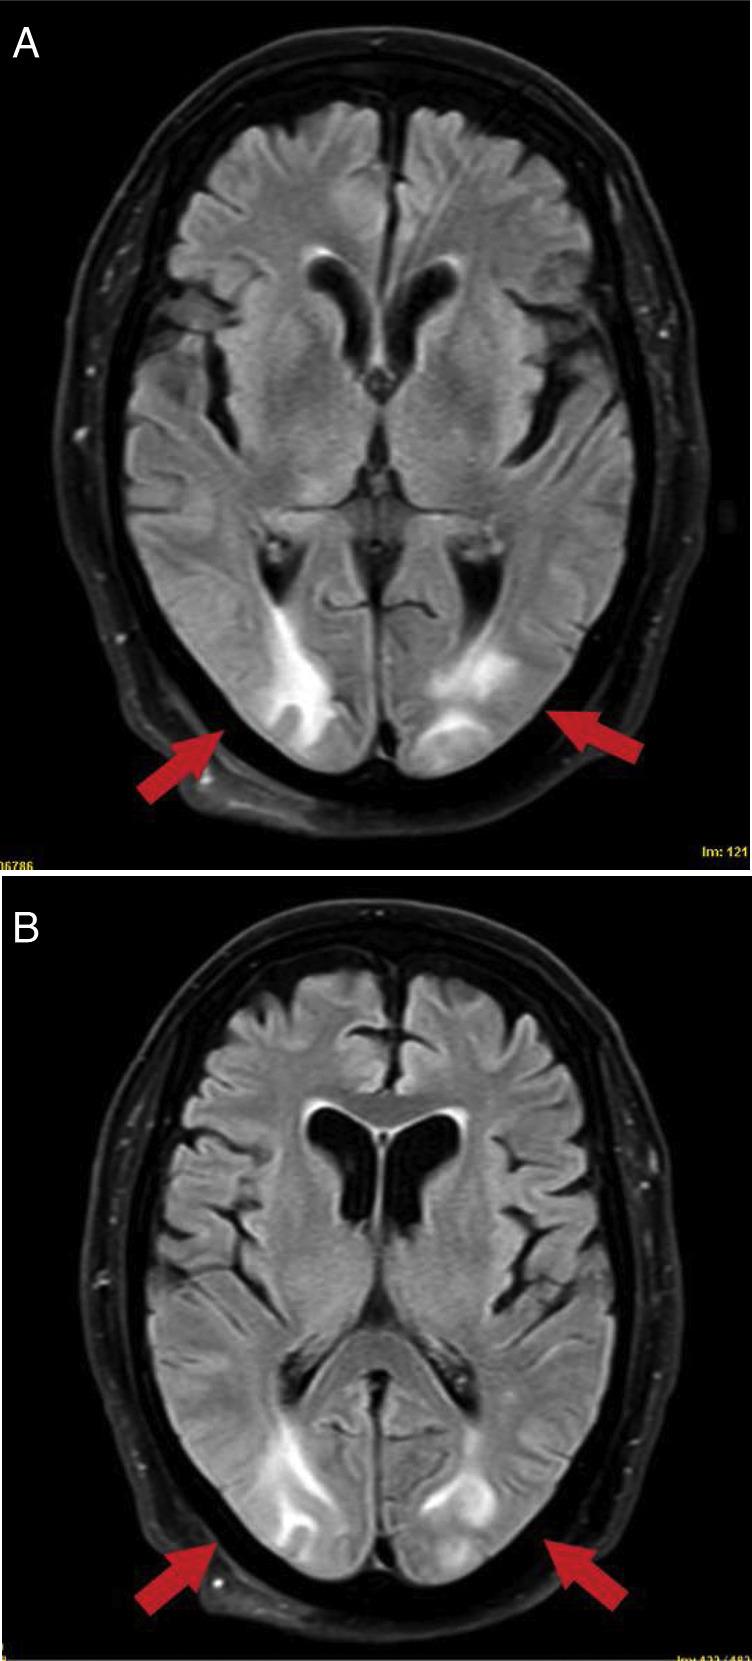

Posterior reversible encephalopathy syndrome is an acute neurological disorder characterized by variable symptoms and radiological images characteristic of vasogenic parietal-occipital edema. It is associated with clinical conditions such as high blood pressure, infection/sepsis, or cytotoxic/immunosuppressive drugs, among others. It is characterized pathophysiologically by endothelial damage with breakdown of blood-brain barrier, cerebral hypoperfusion, and vasogenic edema. The cases are presented on 2 critical COVID-19 patients who were admitted to pneumonia requiring mechanical ventilation and who, after removing sedation, developed acute and reversible neurological symptoms consisting of epilepsy and encephalopathy, associated with hyperintense subcortical lesions on brain magnetic resonance imaging compatible with posterior reversible encephalopathy syndrome. SARS-CoV-2 coronavirus would activate an inflammatory response that would damage brain endothelium. It could be triggered by cytokine release, as well as by direct viral injury, given that endothelium expresses ACE2 receptors. It could explain the possible association between posterior reversible encephalopathy syndrome and COVID-19.